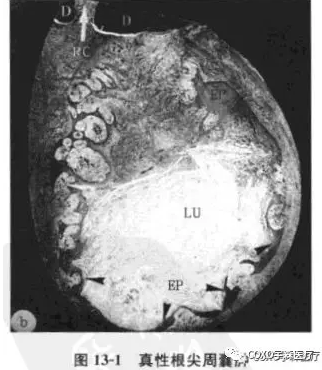

真性根尖周囊腫:包括4個主要成分:

①囊腔;

②囊壁上皮;

③上皮外組織;

④外周環(huán)形排列的膠原纖維。囊腔完全由上皮層包裹與根管隔離,腔內(nèi)一般含有壞死組織,偶爾含有膽固醇晶體。紅細胞和中性粒細胞主要存在于上皮層內(nèi)(圖13-1)